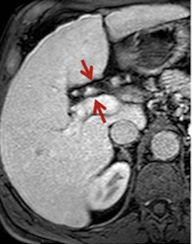

What is this and what type of scan

Cirrhotic liver, CT

Normal liver, CT